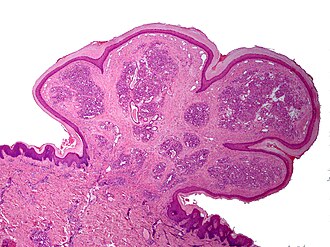

Lobular capillary hemangioma. H&E stain. | |

| LM | polypoid or peduculated lesion, vascular - with plump endothelium, usu. thinned epithelium or ulcerated, lobular arrangement of vascular (seen at low power) |

Features:[4]

- Polypoid or peduculated.

- Vascular, i.e. many blood vessels, with plump endothelium.

- Usu. thinned epithelium[5] or ulcerated.[2]

- Lobular arrangement of vascular (seen at low power).[6]

The sections shows a pendunculated vascular lesion with small capillaries arranged in a lobular fashion. The endothelial cells of the lesion show no atypia. The overlying acanthotic epidermis has hyperkeratosis and hypergranulosis, and is focally ulcerated and impetiginized. There is no significant keratocyte atypia. No melanocytic nests are seen. The dermis has a mild perivascular lymphoplasmacytic infiltrate. The lesion is excised in the plane of section.